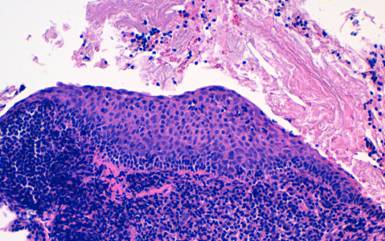

Results of microscopy showed acellular debris with eosinophilic viscous extracellular material and groups of epithelial cells with reactive changes. The cell block showed squamous epithelium overlying dense lymphoid tissue, with secondary follicles. No malignant cells were seen (Figure 3). The appearances were consistent with lymphoepithelial cyst of the pancreas.

Figure 3. H&E section (x200) from the cell block shows acellular cyst contents overlying stratified squamous epithelium. Beneath the epithelium there is dense lymphoid tissue. No dysplastic or malignant change is seen. |